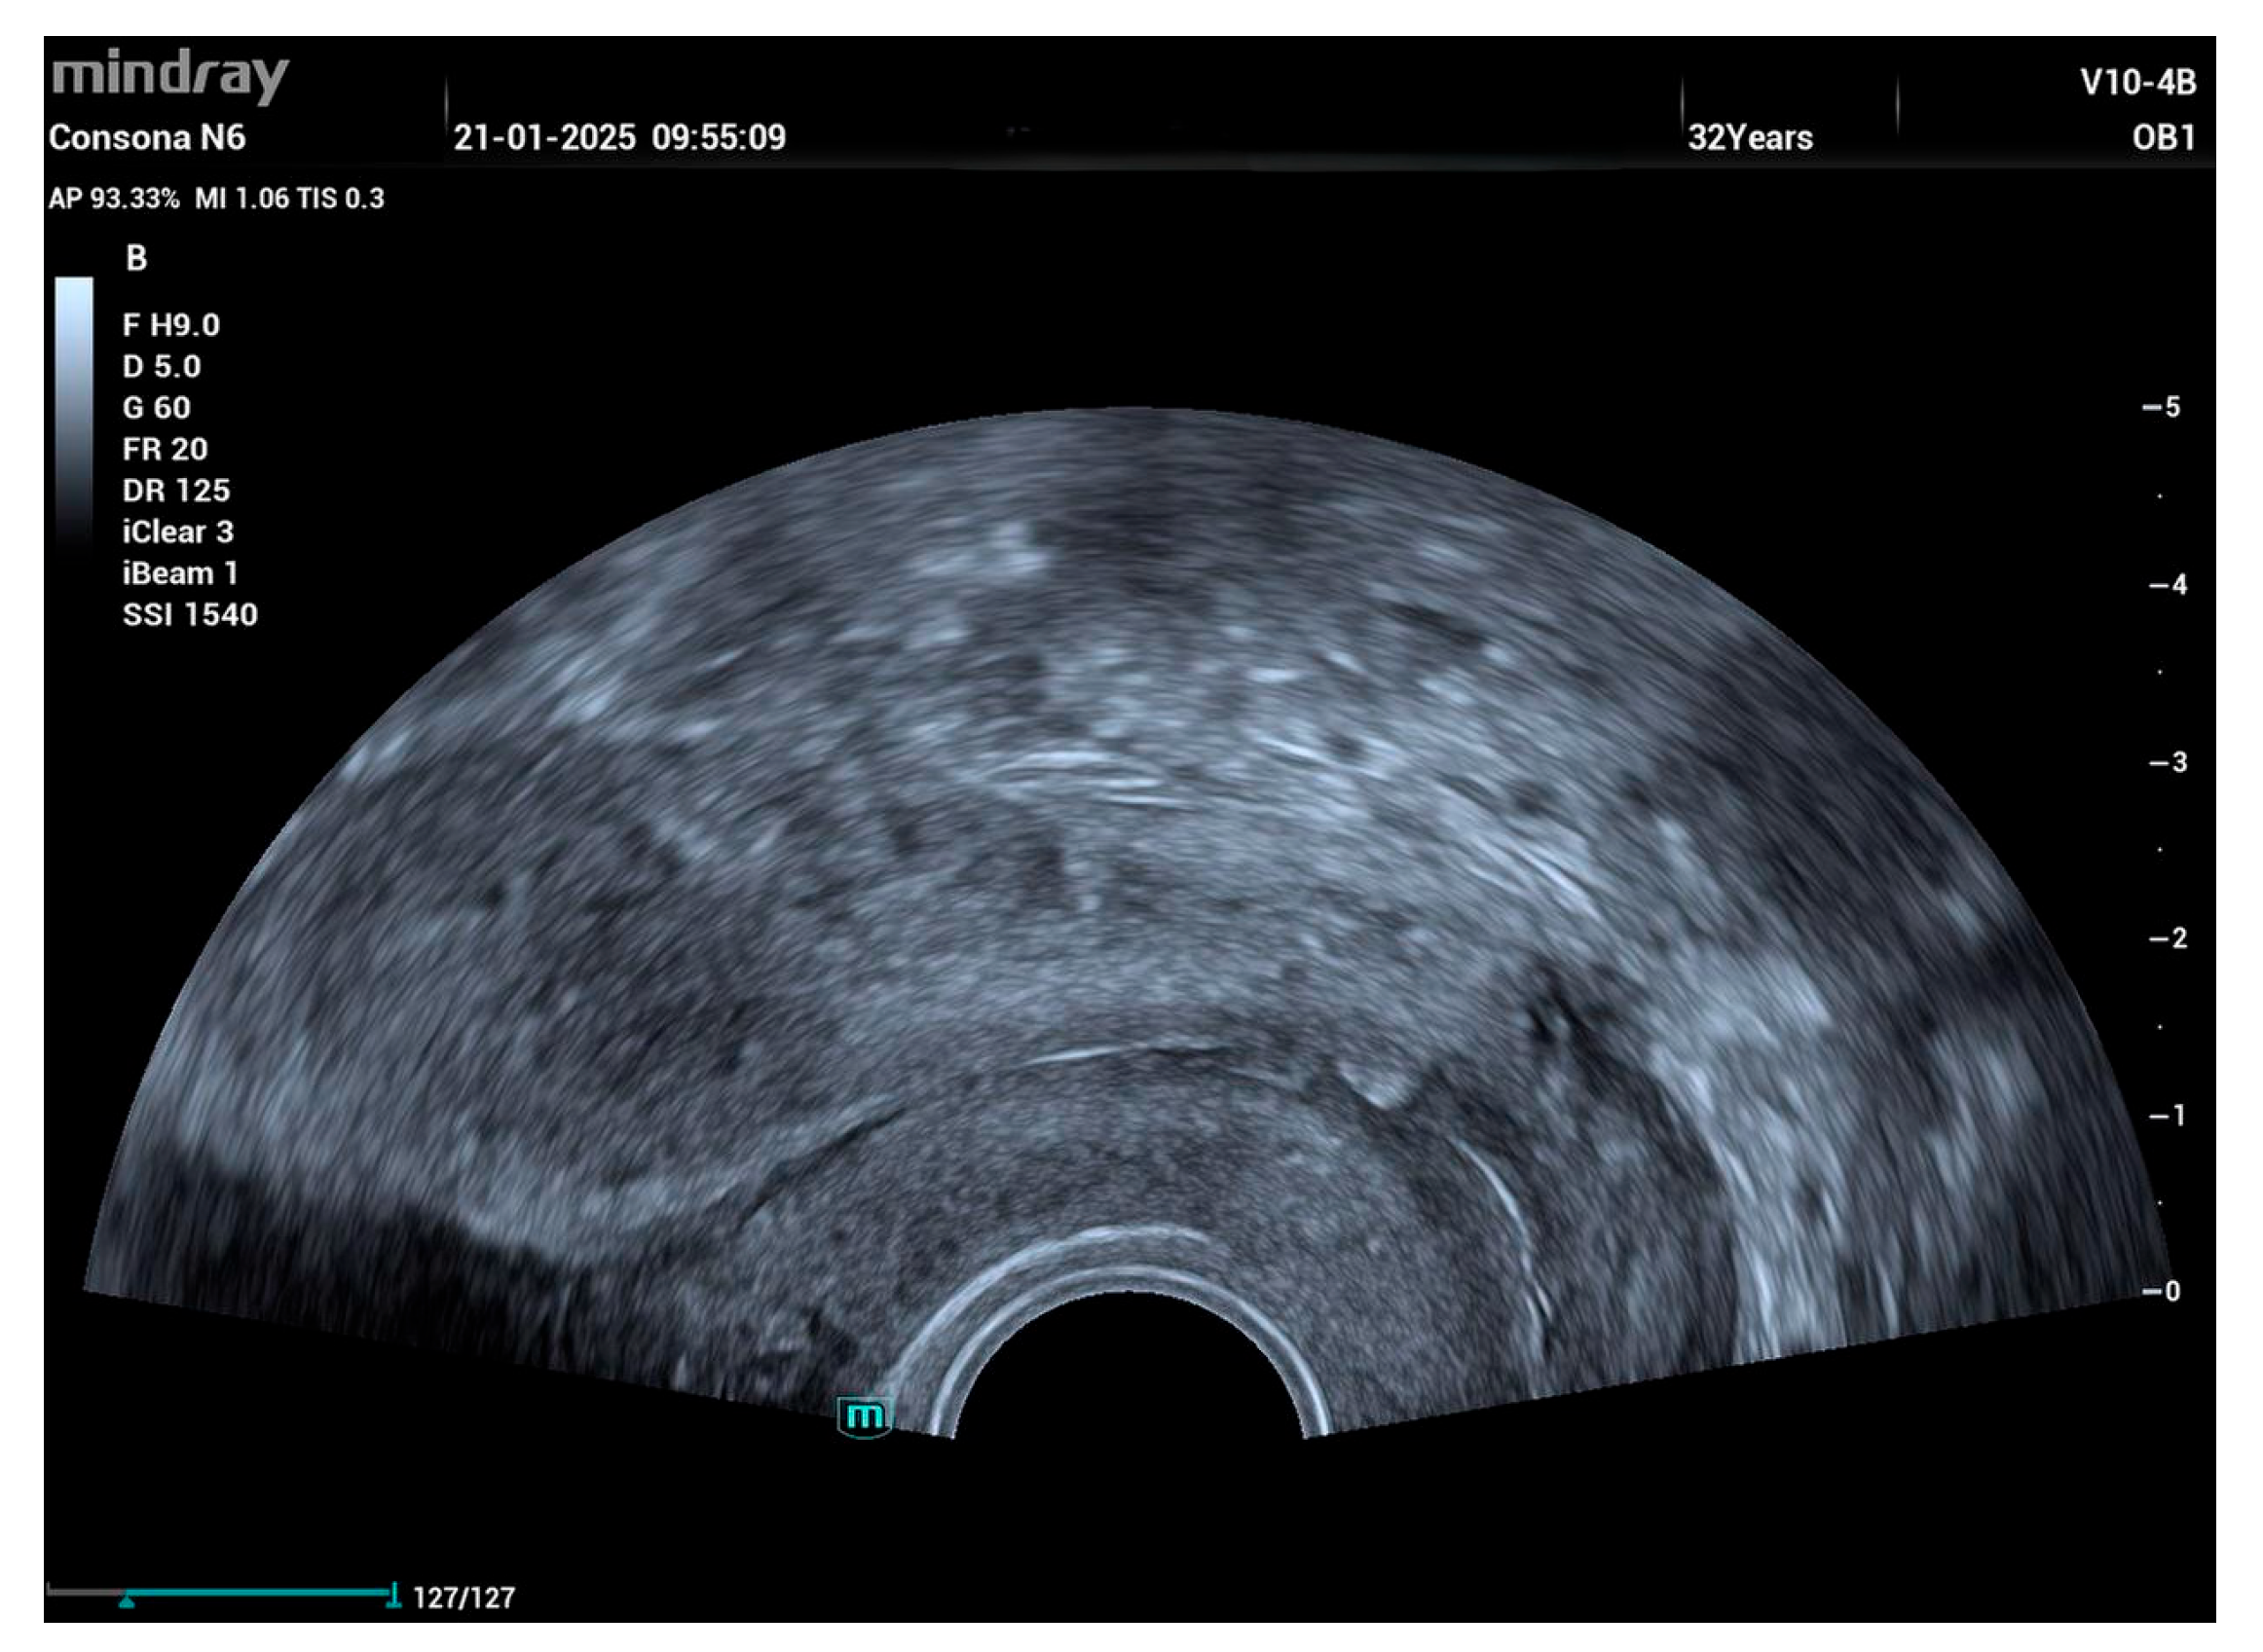

2. Case Report